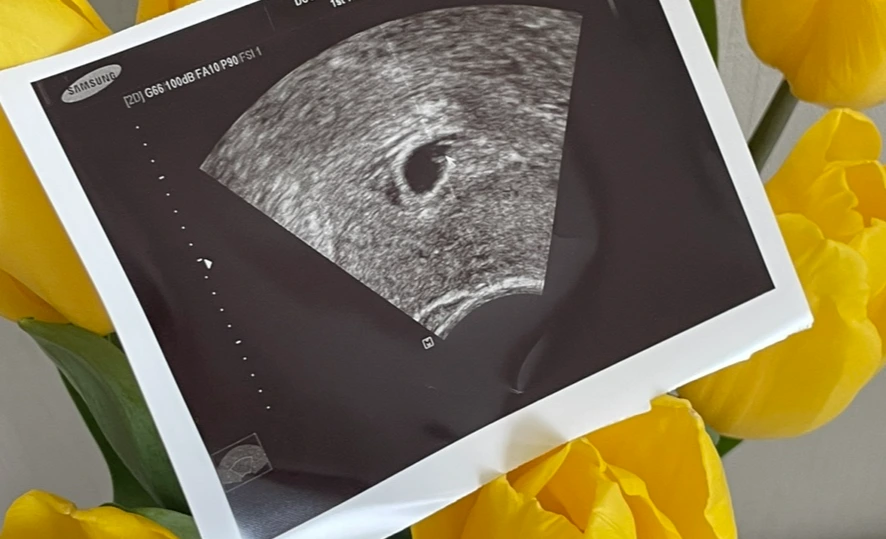

그리고 2주 후, 5주 3일 차가 된 날 초음파로 아기집과 난황을 보았다. 학창 시절 가정 시간에 배웠던 그 임신의 과정이 내 몸에서 직접 일어나다니! 그저 신기할 따름이었다. 산부인과에서 뽑아주신 초음파 사진을 소중히 집에 가져와서, 미리 준비해 두었던 임신 기록장에 꼭 붙여준 후 아기에게 쓰는 일기를 남겼다. 겉에서 보기에는 평소와 다르지 않은 모습이지만 내 뱃속에 새로운 생명이 들어설 준비가 되었다는 것을 확인하고 나니 기분이 몽글몽글해졌다.

IMG_5097.jpg?type=w1 처음 만난 아기집과 난황